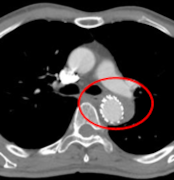

TEVAR前 偽腔開存

TEVAR 2年後 大動脈がremodeling